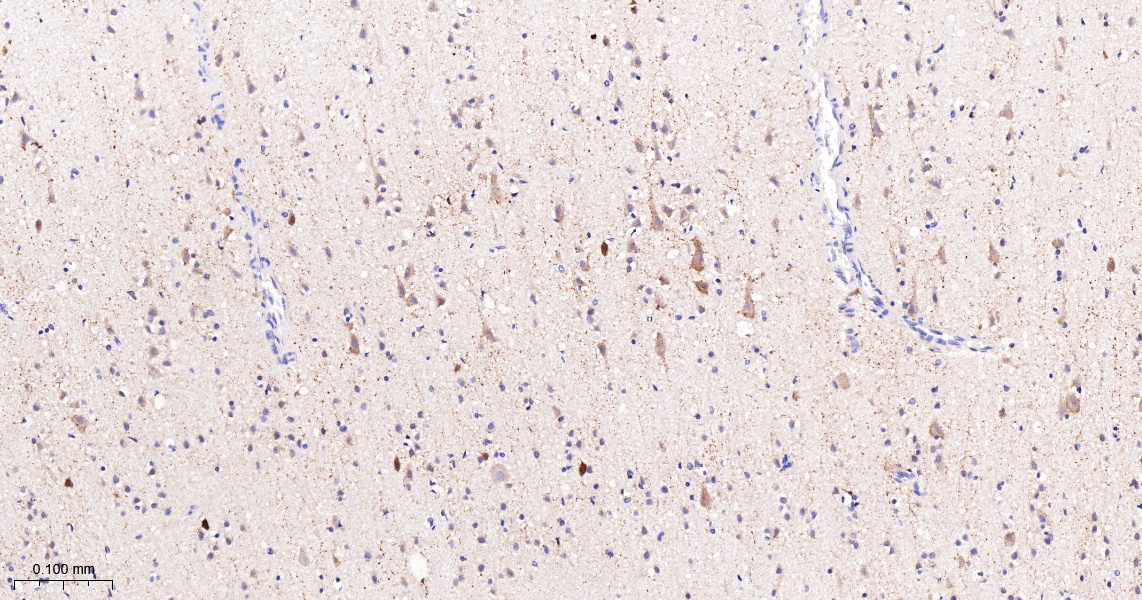

• IHC-P

IHC-P IHC-P1:100-500